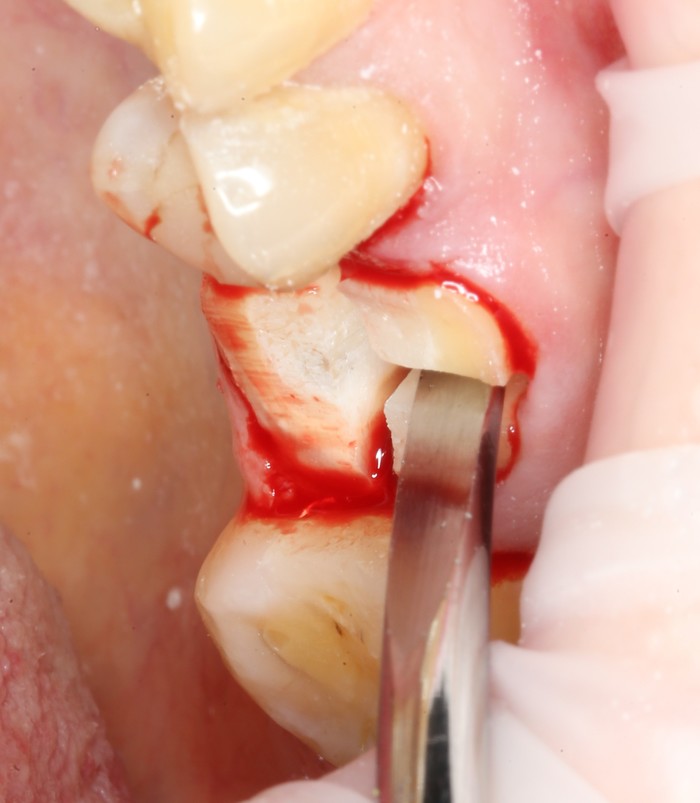

1 – снятие старой коронки.

Было необходимо дождаться, пока десна полностью «не успокоится».

2 – проведение пластики десны.

Был взят трансплантат в области бугра верхней челюсти (это то место, где раньше был зуб мудрости).

После снятия коронки:

Выкрутили абатмент: